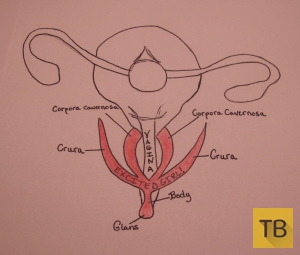

Научное название наружной «маленькой пимпочки» или «шишечки» головка. Этот маленький орган содержит около 8,000 чувствительных нервных волокон - больше чем где бы то ни было еще в человеческом теле и почти в два раза больше, чем в головке пениса! Из чтения работы Мари Бонапарт становится ясно, что она ошибочно полагала, что клитор полностью состоит из головки, а поскольку это единственная видимая часть клитора и к тому же сверхчувствительная, большинство современных женщин делают то же неверное заключение. Однако на самом деле большая часть клитора расположена внутри и состоит из двойного пещеристого тела (лат. corpus cavernosum clitoridis), двух ножек (лат. crus clitoridis) и двух клиторальных луковиц (лат. bulbus vestibuli vaginae).

Головка клитора переходит в тело внутреннего клитора, которое в свою очередь расходится в два пещеристые тела. В возбужденном состоянии пещеристые тела охватывают влагалище с обеих сторон, как если бы они крепко обнимали его!

Рисунок клитора в возбужденном состоянии (надписи на рисунке: Vagina или Va - влагалище, Uterus - матка Fallopian Tube – фаллопиева труба, Ovary - яичник, Bladder – мочевой пузырь, Urethra - уретра, Glans – головка клитора, Body – тело клитора, Corpus Cavernosum – двойное пещеристое тело клитора, Crura – ножка клитора).

Пещеристые тела уходят еще глубже, сходясь и вновь раздваиваясь, чтобы сформировать две ножки. В состоянии покоя эти ножки длиной до 9 см направлены в сторону бедер, при возбуждении они вытягиваются в сторону позвоночника.

Около каждой ножки с обеих сторон от входа во влагалище расположены клиторальные луковицы. Они находятся внутри тела под большими половыми губами. Когда они наполняются кровью, они замыкаются вокруг отверстия влагалища, вызывая набухание вульвы. Возбудите их и вы получите более возбужденный, более тесный вход во влагалище для исследования!

Рисунок клитора в возбужденном состоянии (надписи на рисунке: Vagina - влагалище Glans – головка клитора, Body – тело клитора, Corpus Cavernosum – двойное пещеристое тело клитора, Crura – ножка клитора).